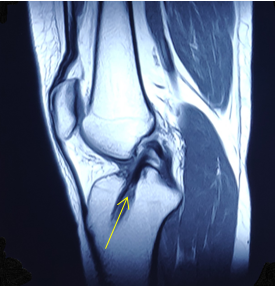

前交叉韧带损伤在儿童和青少年中越来越常见,损伤主要表现为两种形式:韧带实质部损伤和胫骨髁间棘撕脱骨折,团队经过20年的努力,已经将诊断及治疗流程标准化,目前正在科室行政主任杨征带领下承担北京市卫健委迎冬奥国际合作择优资助基金项目:中国儿童青少年前交叉韧带实质部损伤和胫骨髁间棘撕脱骨折诊疗指南的编写工作。

前交叉韧带损伤,箭头为前交叉韧带